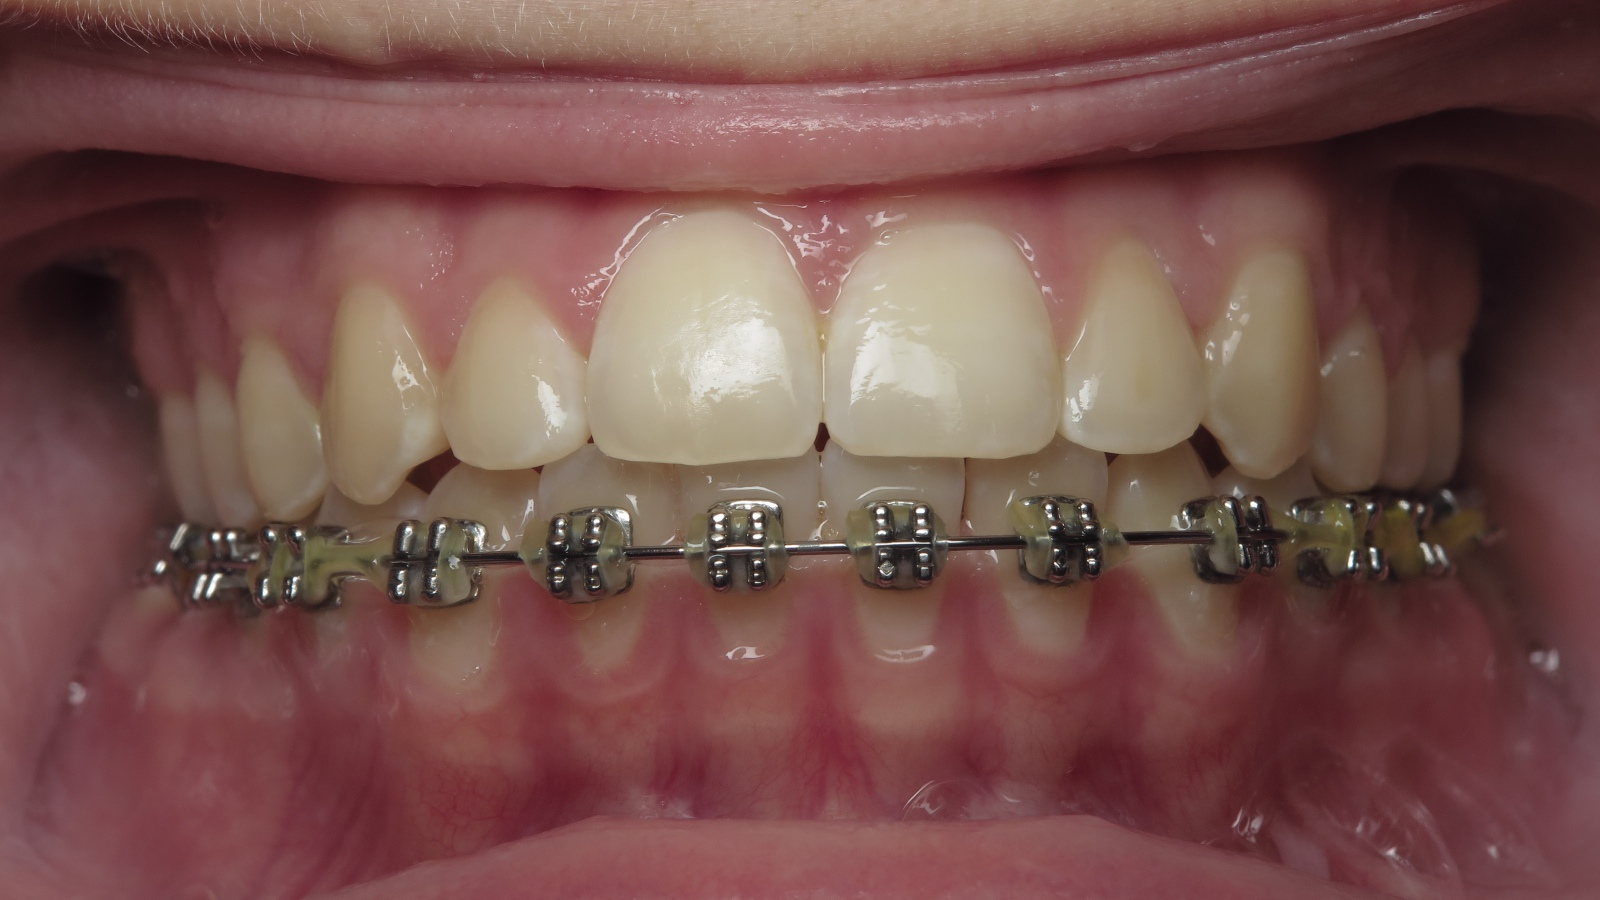

appareillage multibagues traitement en cours